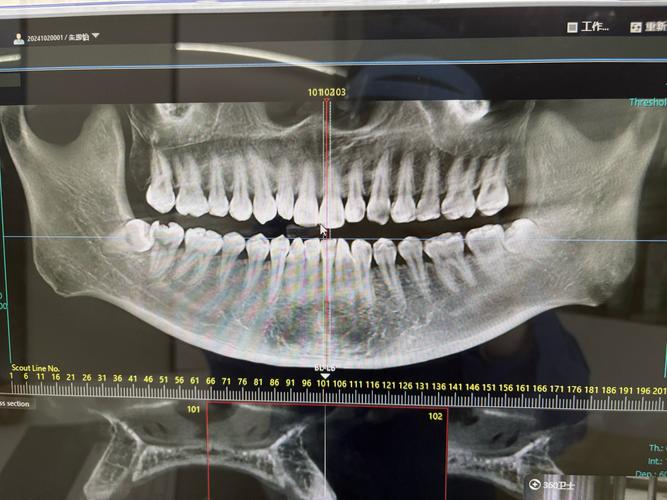

| 全景片(曲面断层片) | 全口牙齿、牙槽骨、颌骨、颞下颌关节、上颌窦、下颌神经管等 | 观察牙齿数量(是否有埋伏牙、多生牙、缺失牙)、牙根形态、牙槽骨密度、骨皮质厚度等,初步判断颌骨内是否有病变。 |

| CBCT(锥形束CT) | 口腔颌骨的三维立体影像,可任意层面重建(冠状位、矢状位、横断面) | 精确观察牙根位置、牙根间距、骨量是否充足、埋伏牙的具体位置与方向、邻牙牙根是否受压,是复杂病例(如正畸-正颌联合治疗)的必备工具。 |